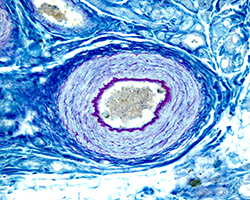

Aparato circulatorio

Aparato circulatorio

Corazón, arterias, venas y pequeños vasos.

(12 preparaciones) -